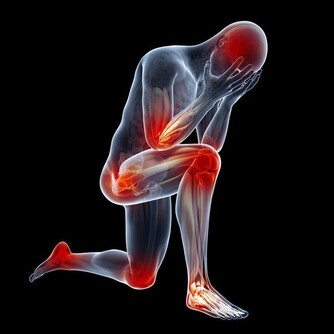

三月初,我的頸椎出了一點問題,整個人的精神狀態都很不好,睡覺不舒服,也不能長期坐在電腦面前。

我在想著,我還這麼年輕,頸椎怎麼就開始出問題了?那以後我怎麼辦?

可是我又非常清楚,長期在電腦面前工作,頸椎出問題也在預料之中。

再想起頸椎不舒服的那段時間裡,我明白這是對我的一種預警,警告著我:如果你再這樣下去,你的頸椎真的會出問題的。

直到現在,我都不會讓自己長時間緊繃在電腦面前了。寫稿斷片的時候,我就站起來活動活動,伸伸懶腰,讓肌肉不那麼緊繃,或者聽會音樂,放鬆一會兒。